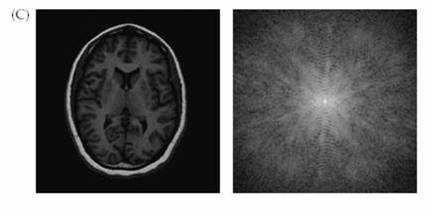

Figure 4. Image and

k-space. The data from the scanner is k-space data. The image space data

is a Fourier transform of the k-space data. (Figures courtesy of Huettel et al.)